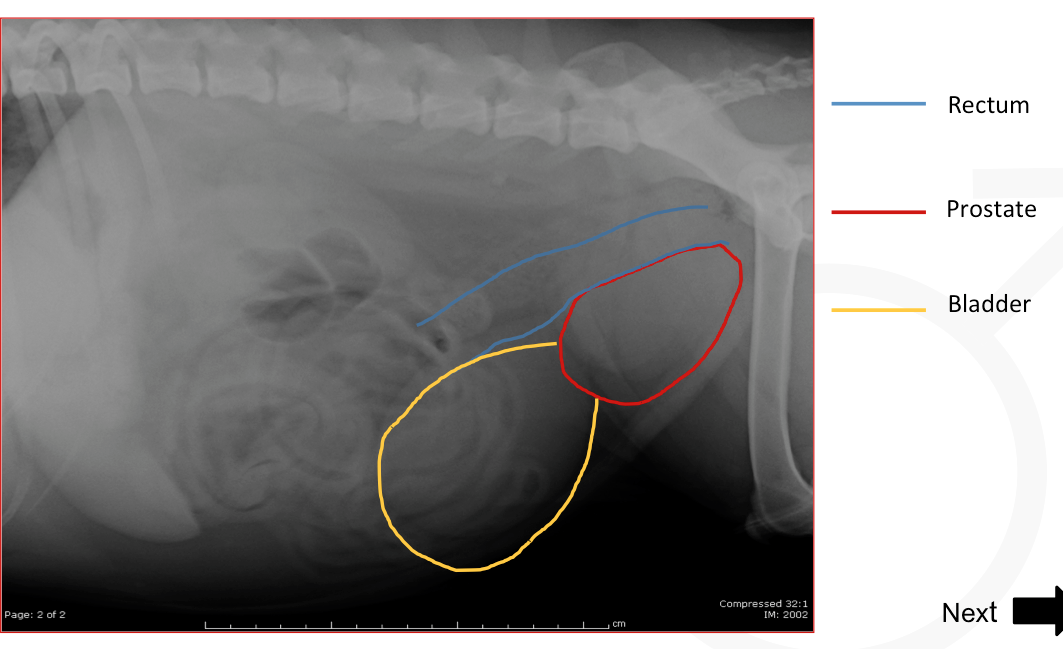

Rectum, prostrate, and bladder location in a dog